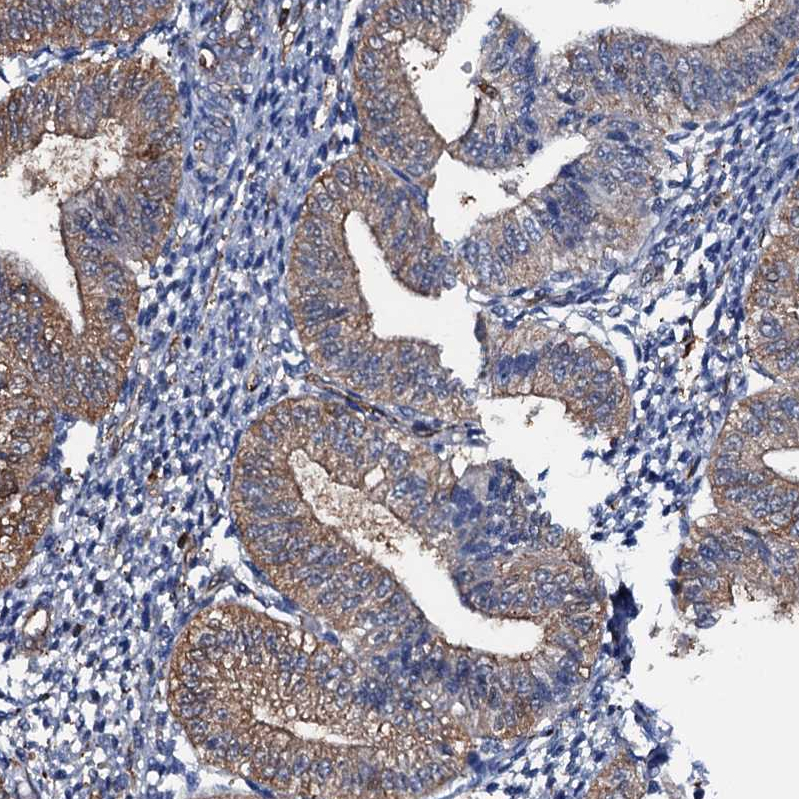

Immunohistochemical staining of human tonsil shows strong membranous-cytoplasmic positivity in non-germinal center cells and germinal center cells.